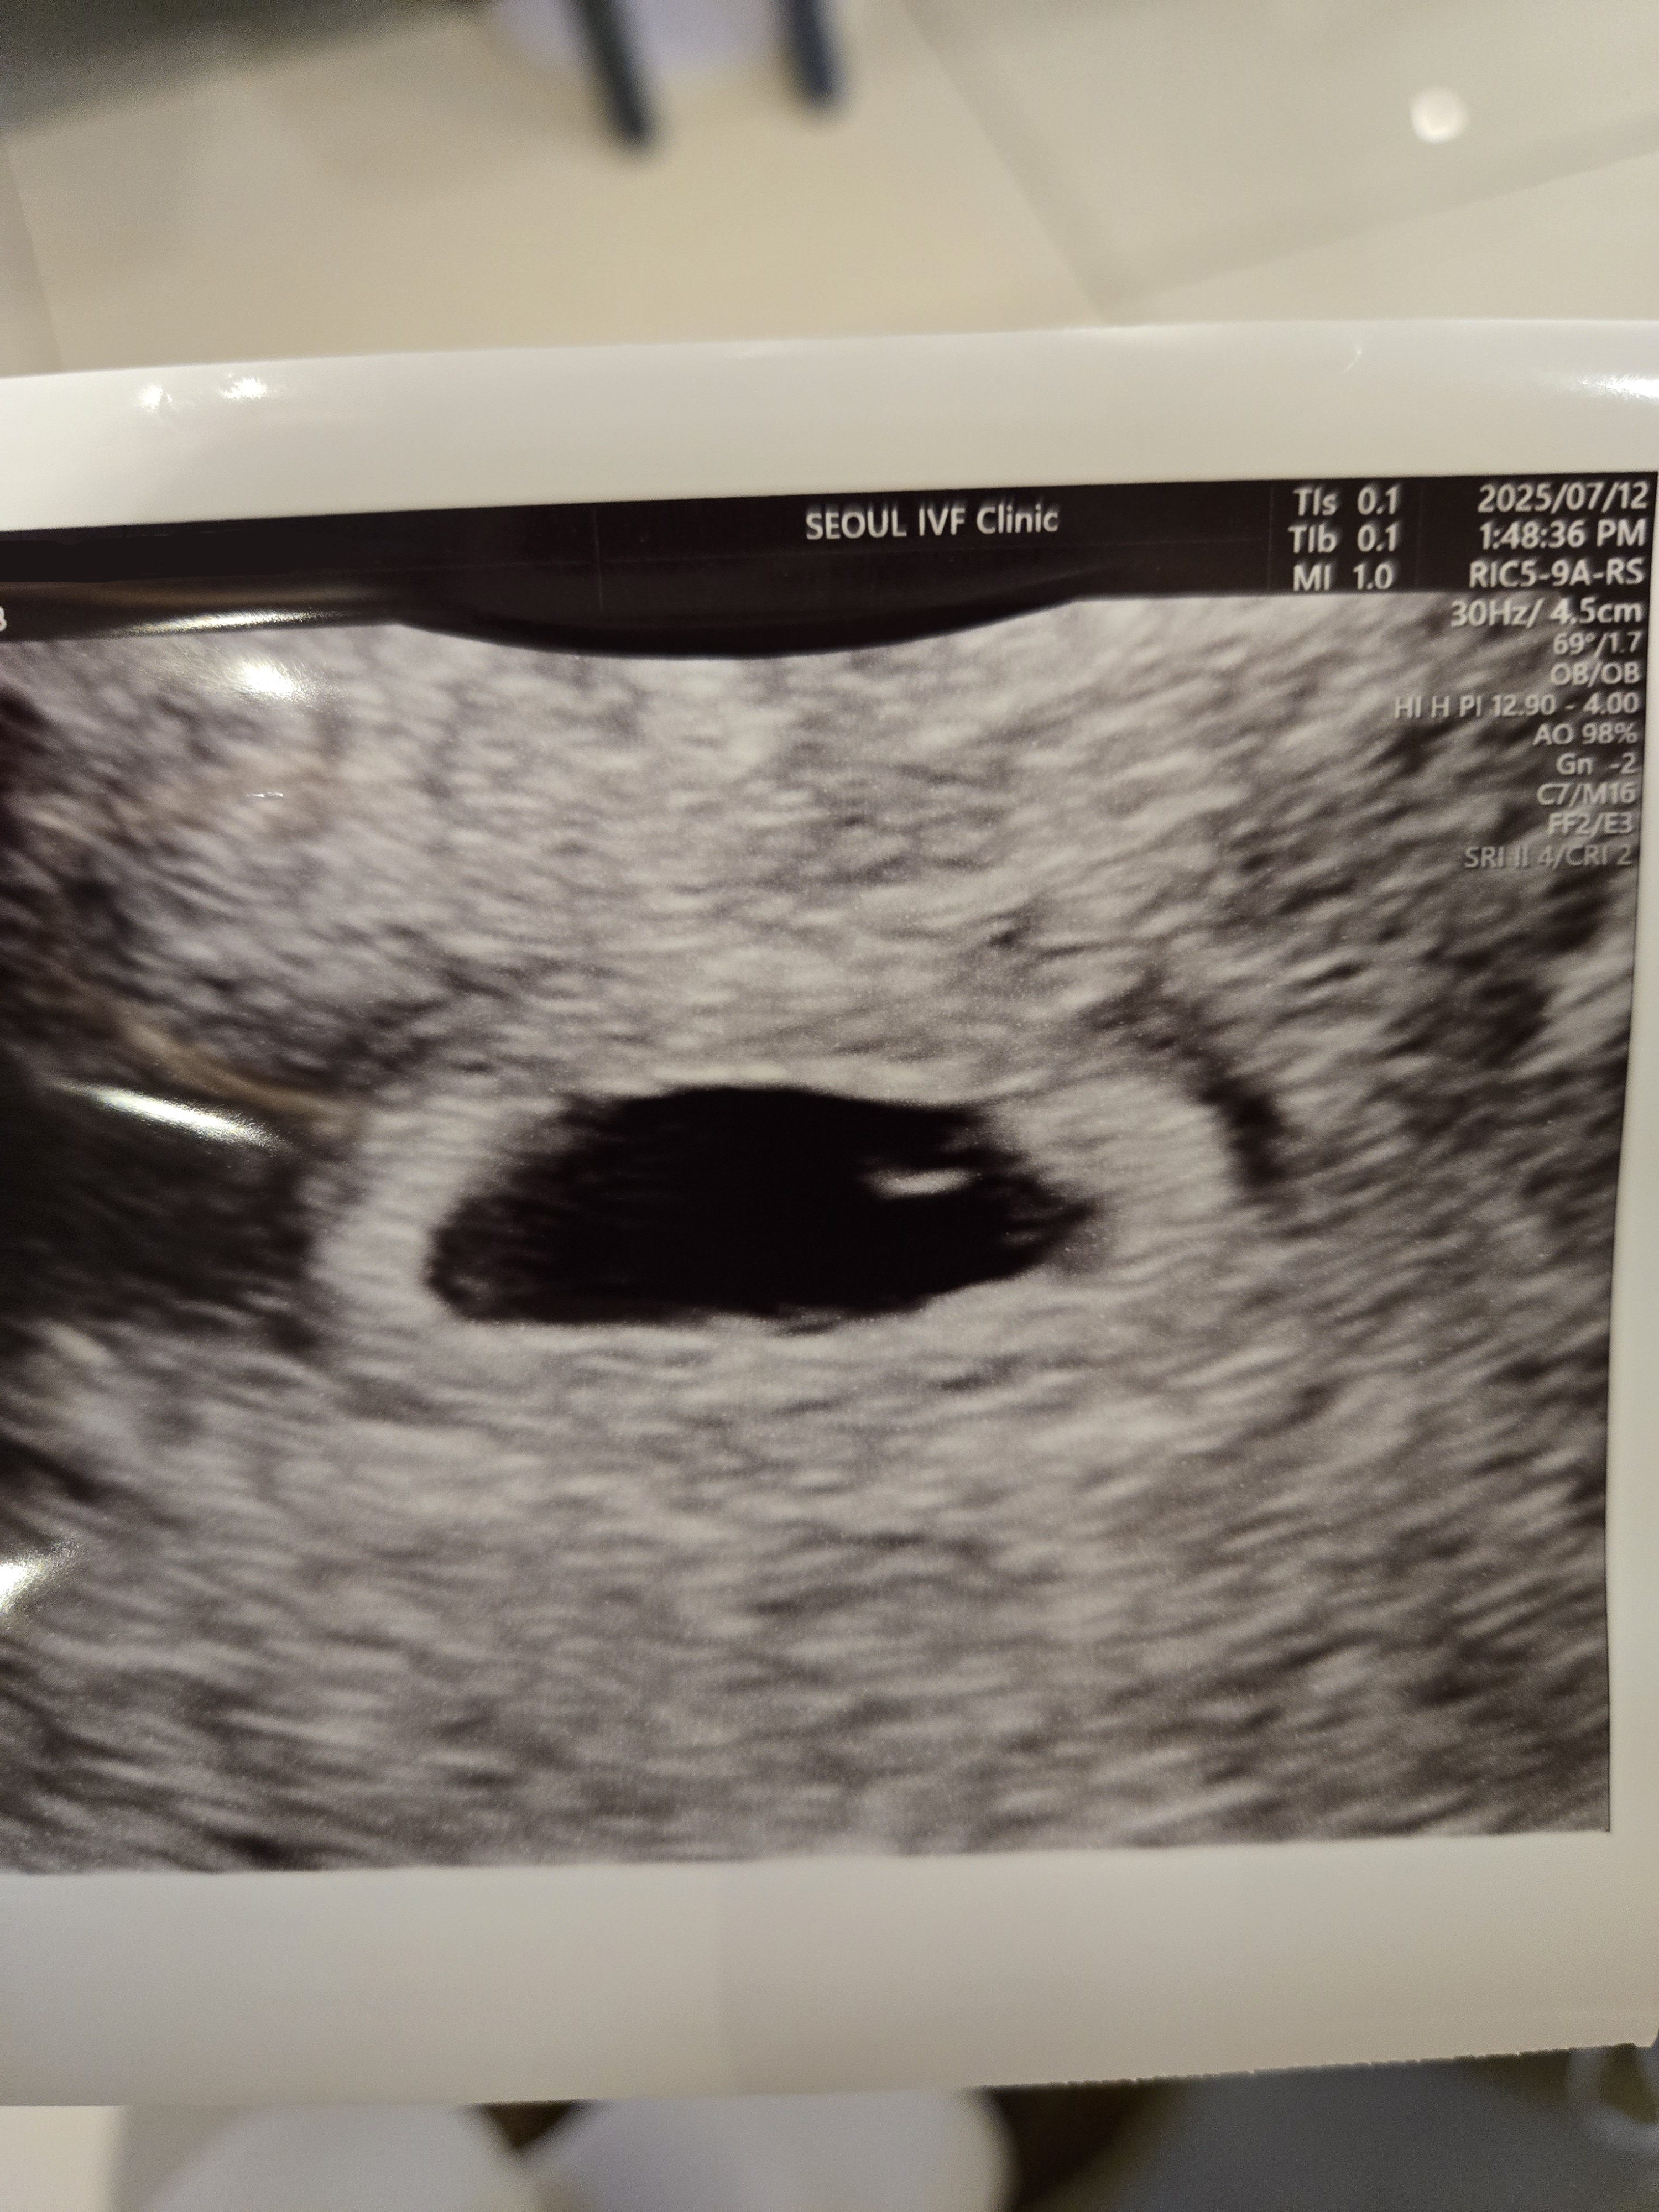

| 가슴 떨리는 임신 이야기를 공유해 주세요. | 저희 부부는 신혼생활 후 임신 계획을 세우고 있었습니다. 그러나 우연히 난임의 원인을 알게 되면서 여러 병원을 다니며 치료와 시술을 반복해야 했습니다. 서로 많이 지치기도 했지만 포기하지 않고 노력했습니다. 특히 시험관 1차 실패 후 몸과 마음이 모두 힘들어 거의 포기할 뻔했을 때, 우연히 서울IVF 이경훈 원장님을 알게 되었고 운명처럼 병원을 찾게 되었습니다. 원장님의 따뜻한 격려와 응원 덕분에 결국 그토록 원하던 아기를 만나게 되었습니다. |

| 치료 도중 느꼈던 가장 기뻤던 순간과 절망적인 것들은 무엇인가요? 잊지 못할 경험이 있나요? | 가장 절망적이었던 순간은 첫 번째 시험관이 실패로 끝났을 때였습니다. 몸도 마음도 지쳐 병원에 가는 것조차 힘들 정도였지요. 반대로 가장 기뻤던 순간은 서울IVF에서 임신 결과를 확인하고, 이경훈 워장님과 의료진분들께 진심 어린 축하를 받았을 때였습니다. 이전 병원들에서는 느껴보지 못했던 따뜻한 분위기였기에 더 큰 감동으로 다가왔습니다. |